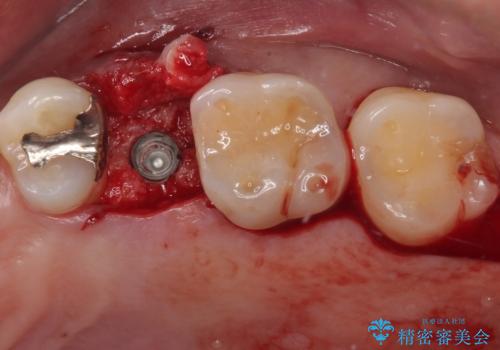

インプラント埋入時に十分な安定性が確認できたため、当日仮歯を装着しました。

埋入から2ヶ月ほどでインプラントの十分な生着が認められ、処置した歯肉も綺麗に治癒したため、速やかに補綴治療を行いました。

補綴治療後3ヶ月での経過は良好で、引き続き経過観察を行っていきます。